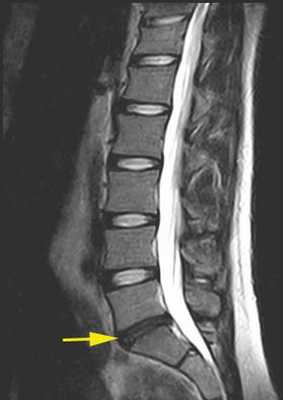

Больной обследован. При спондилографии грудного отдела позвоночника выявлен остеохондроз Th III —Th IV , II период, Th VIII —Th XII III период; данные MPT грудного отдела позвоночника: грыжи межпозвонковых дисков Th III —Th IV , Th IX —Th X , Th X —Th XI (рис. 1). При электронейромиографии нижних конечностей обнаружены выраженные изменения по аксональному типу в левом и правом малоберцовом нервах.

Рис. 1. Магнитно-резонансные томограммы грудного отдела позвоночника (Т1 режим): в аксиальной (а, б) и сагиттальной (в) плоскостях до операции.

Проведена МРТ (рис. 2): компрессия спинного мозга устранена. Больной переведен в неврологическое отделение для восстановительного лечения.

Рис. 2. Магнитно-резонансные томограммы грудного отдела позвоночника (Т1 режим): в аксиальной (а, б) и сагиттальной (в) плоскостях через 2 нед после операции.